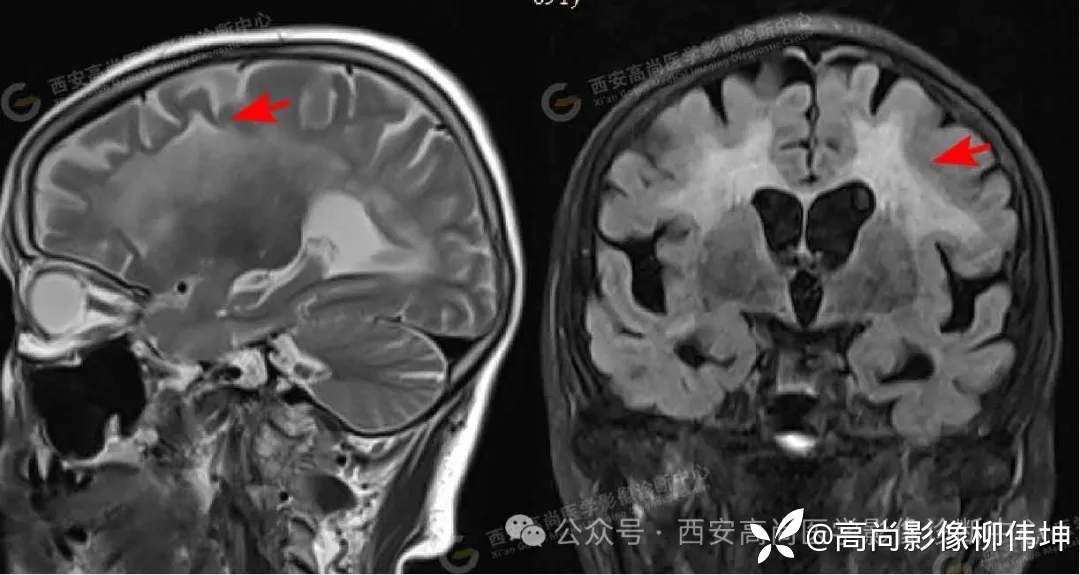

MR影像图

矢状位 T2WI 冠状位 FLAIR

MR平扫+DWI+MRS:双侧额叶、半卵圆中心、侧脑室旁、胼胝体白质区见片状稍长T1稍长T2信号,FLAIR像显示高信号,边缘模糊,DWI像上病灶边缘见条片状高信号,ADC图上呈稍低信号,MRS示:上述病灶CHO波未见增高,NAA波未见减低,CHO/NAA为0.58。

诊断:双侧额叶、半卵圆中心、侧脑室旁、胼胝体区对称性脑白质脱髓鞘,考虑神经元核内包涵体病可能。

影像表现:皮髓质交界区广泛DWI鸡冠花样、曲线样高信号、胼胝体DWI高信号、对称性脑白质病变、皮层肿胀、广泛性脑萎缩。

(3)对称性脑白质病变

显著累及放射冠和半卵圆中心部位的白质病灶。